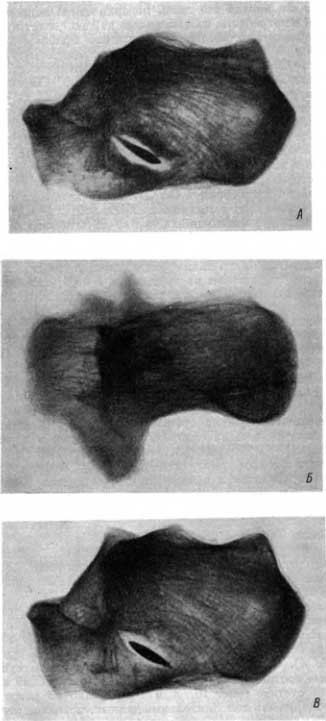

Специального внимания заслуживает скелет зрелой женщины из погребения в Саркеле. Осмотр левой половины таза и левого бедра создали впечатление лишь вывиха бедренной кости кверху и кзади с образованием новой суставной впадины (неоартроз), с запустением старой суставной впадины (рис. 16, А). Сочленяющиеся поверхности в новом суставе имели мощные краевые костные разрастания, т. е. деформирующий артроз в новообразованном суставе (рис. 16, А и Б). Однако на рентгенограммах можно было обнаружить дополнительные данные, позволившие внести существенные коррективы в трактовку происхождения анатомически установленных изменений. Отчетливо выступала картина старого сросшегося вколоченного перелома шейки бедра непосредственно под головкой. Это так называемый субкапитальный перелом (рис. 16, В). Таким образом, у этой женщины одновременно с переломом шейки бедра произошел вывих в этом тазобедренном суставе. Женщина жила много лет после травмы; она была инвалидом, сильно хромала вследствие значительного укорочения левой конечности и ограничения подвижности в новообразованном суставе. Этот анатомический препарат является музейной ценностью. Он представляет редкую и поучительную иллюстрацию сросшегося субкапитального перелома шейки бедра с вывихом и образованием нового сустава и возникновения деформирующего артроза в новообразованном суставе. Помимо описанных изменений, у этой женщины имелся старый перелом лучевой кости.

Рис. 16. А — старый вывих в тазобедренном суставе вверх и кзади, резко выраженный деформирующий артроз; Б — рентгенограмма с костей тазобедренного сустава, новообразованный сустав; В — дополнительная рентгенограмма с бедренной кости, хороню виден старый сросшийся перелом шейки бедра.